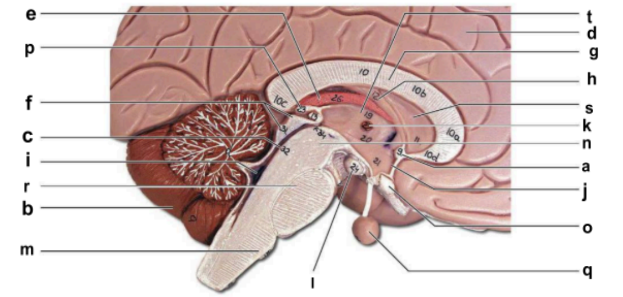

Identify the structure labeled “a” in the image.

anterior commissure

Identify the structure labeled “b” in the image.

cerebellum

Identify the structure labeled “c” in the image.

cerebral aqueduct

Identify the structure labeled “d” in the image.

cerebral hemisphere

Identify the structure labeled “e” in the image.

choroid plexus

Identify the structure labeled “f” in the image.

corpora quadrigemina

Identify the structure labeled “g” in the image.

corpos callosum

Identify the structure labeled “h” in the image.

fornix

Identify the structure labeled “i” in the image.

fourth ventricle

Identify the structure labeled “j” in the image.

hypothalamus

Identify the structure labeled “k” in the image.

interthalamic adhesion

Identify the structure labeled “l” in the image.

mammilary body

Identify the structure labeled “m” in the image.

medulla oblongata

Identify the structure labeled “n” in the image.

midbrain

Identify the structure labeled “o” in the image.

optic chiasma

Identify the structure labeled “p” in the image.

pineal gland

Identify the structure labeled “q” in the image.

pituitary gland

Identify the structure labeled “r” in the image.

pons

Identify the structure labeled “s” in the image.

septum pellucidum

Identify the structure labeled “t” in the image.

thalamus